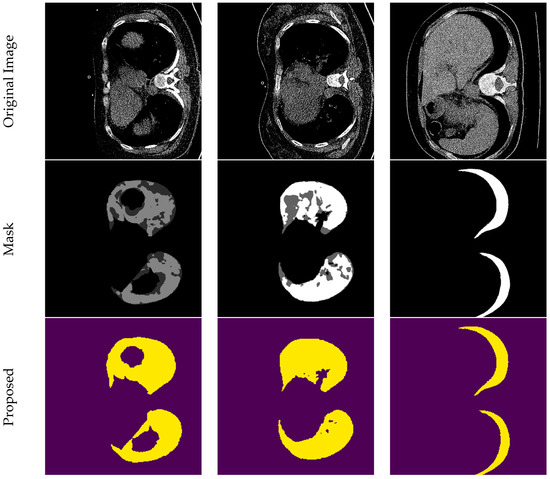

A Multi-Level Cross-Connected U-Net Architecture for Image Segmentation

by Lütfü Bayrak, Ahmet Çinar and Cebrail Barut

Appl. Sci. 2026, 16(6), 2655; https://doi.org/10.3390/app16062655 - 11 Mar 2026

Existing encoder–decoder architectures operating in the field of deep learning-based image segmentation face fundamental limitations such as information loss, performance degradation as network depth increases, and high computational costs. To overcome these issues, we propose a new architecture that integrates features from different [...] Read more.

Existing encoder–decoder architectures operating in the field of deep learning-based image segmentation face fundamental limitations such as information loss, performance degradation as network depth increases, and high computational costs. To overcome these issues, we propose a new architecture that integrates features from different depth levels at a single fusion point. This approach enables both comprehensive representation power and the preservation of very small details. The proposed approach creates an efficient structure that achieves high accuracy values without requiring unnecessary network deepening. The designed model was comprehensively compared with state-of-the-art architectures such as U-Net, V-Net, W-Net, T-Net, Seg-Net, and Multiple U-Net, which are accepted in the literature, on datasets with different characteristics such as MedSeg, Retina Drive, and Massachusetts datasets. Experimental findings reveal that the developed method outperforms its competitors in all test metrics. In particular, the dice (DSC) score, the most critical indicator of segmentation accuracy, achieved a value of 0.957 on the Retina DRIVE dataset, demonstrating a significant performance difference compared to existing models that remained in the 0.68–0.81 range in challenging scenarios. Furthermore, the 99.6% accuracy (Acc) and 0.006 loss (Loss) values obtained on COVID-19 CT data confirm the architecture’s error-free learning capacity. The stable loss function trend observed across all datasets demonstrates the model’s stable learning ability and high generalization capability. Full article